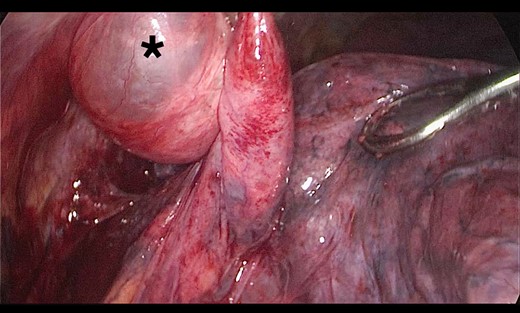

A 73-year-old male patient with a clinical history of COPD, lung emphysema and a 30-year smoking history was admitted to the ED due to a 24-h clinical picture of dyspnea immediately following a sudden bout of dry coughing. Physical examination showed a dyspneic patient, tachypnea of 25 rpm, heart rate of 85 bpm and blood Pressure of 135/75 mmHg along with central cyanosis. Chest exam showed a hyper-resonant right hemithorax along with reduced breath sounds. Initial chest X-ray revealed a large right-sided pneumothorax (Fig. 1). A right chest tube was placed in the ED. Emergency echocardiogram had no significant findings and spirometry showed suspected patterns of obstruction. Following patient stabilization, a high-resolution chest computed tomography (HRCT) was performed revealing extensive pan lobar emphysema throughout both lungs, para septal emphysema in both the anterior upper lobes and herniation of a left lung bullae through the anterior mediastinal pleura along with a right-sided pneumothorax with the chest tube in place with persistent air space (Fig. 2). The patient was taken to surgery where a right video-assisted thoracoscopic (VATS) approach showed severe lung emphysema and a contralateral herniated left lung bulla through the mediastinal pleura anterior to the pericardium (Fig. 3). Right pleurodesis was performed using Talc and a left posterior thoracoscopy showed a severe emphysematous left lung with a lingular herniated bulla to the right hemithorax through an anterior mediastinal pleural defect along with pleural adhesions (Figs 4 and 5). Thoracoscopic hernia reduction was performed along with bullectomy using 60 mm mechanical sutures (Fig. 6). Chest tubes were removed on POD 3 (right) and POD 4 (left). The patient had significant respiratory improvement and was discharged on POD 5.

Thoracoscopic view from left side of transmediasinal hernia of pulmonary bulla after reduction (asterisk).